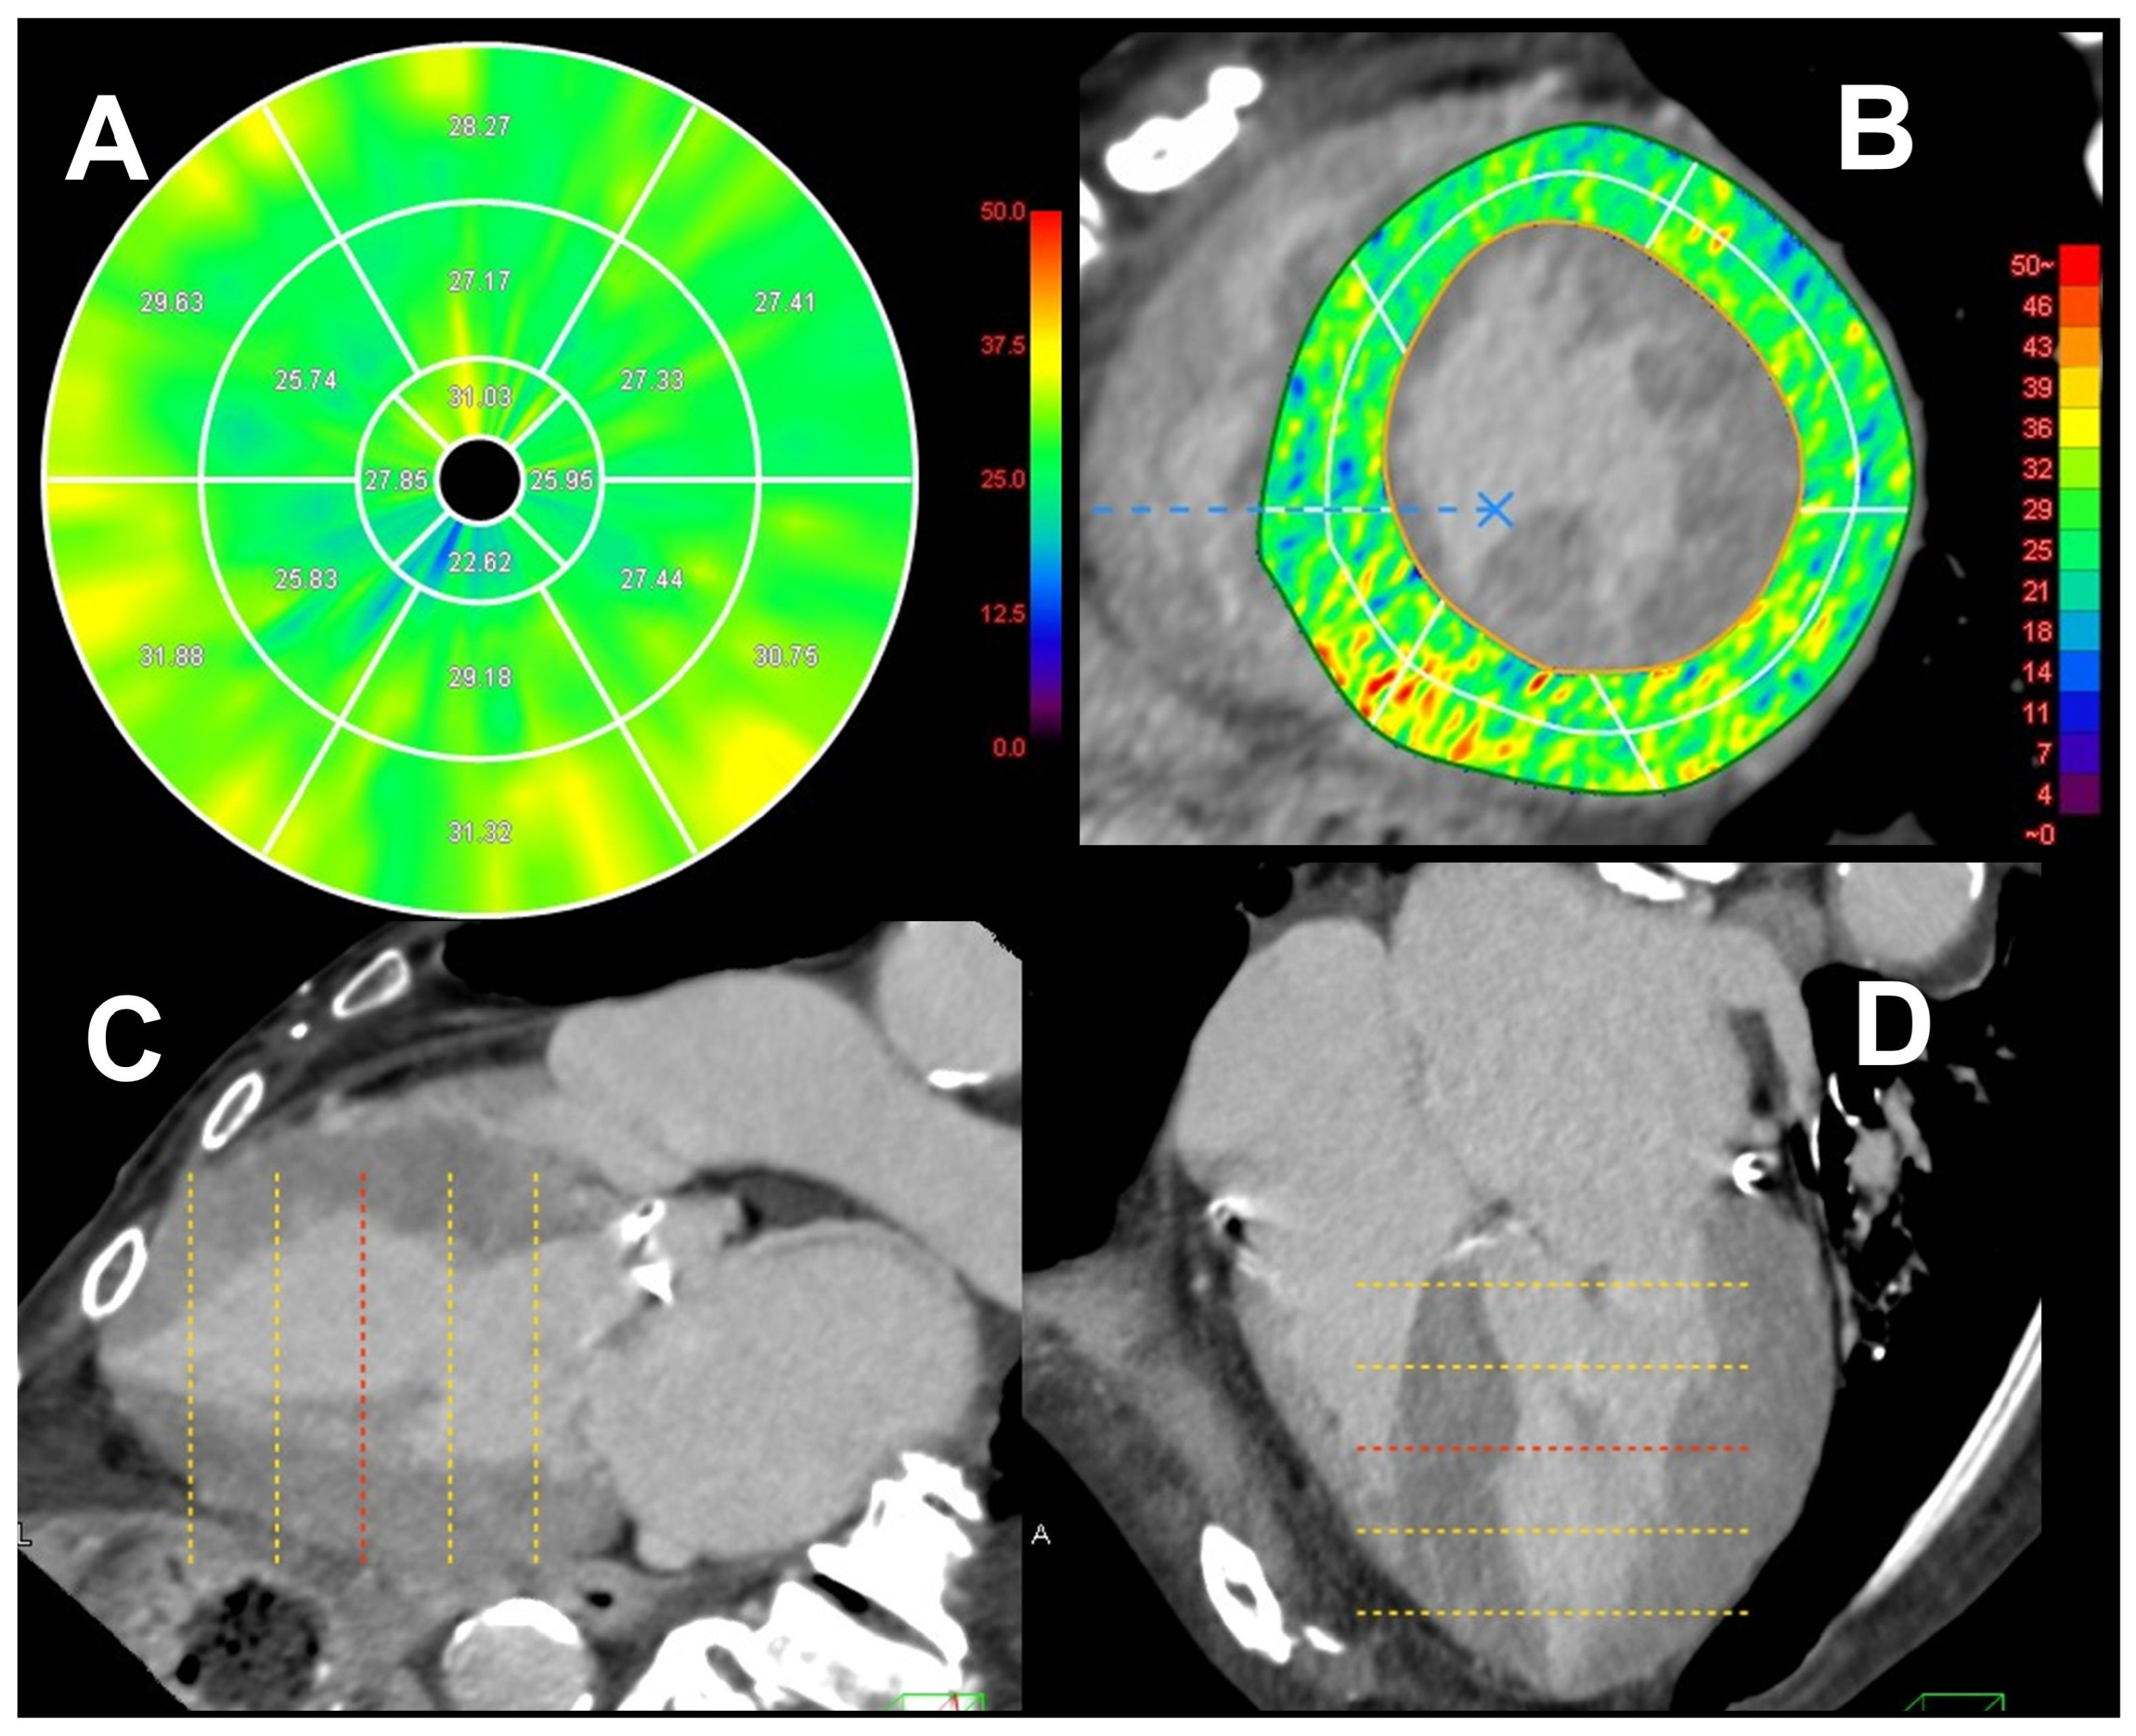

2.2. Analysis of ECV in CT